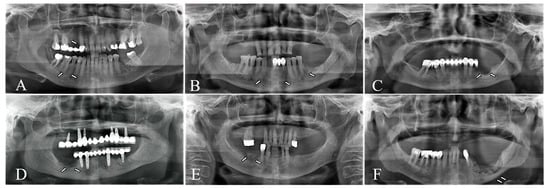

Each parameter was coded dichotomously (present/absent) on both baseline (T0) and 6-month follow-up (T1) radiographs, and temporal changes documented. Edentulous regions were excluded from lamina dura assessment, and periosteal reactions were not evaluated in maxillary MRONJ sites when reliable visualization was not possible. Representative radiographs illustrating these features are shown in Figure 1.

Figure 1. Radiographic parameters evaluated on digital panoramic radiographs. (A) lamina dura thickening, (B) trabecular bone alteration, (C) osteosclerosis, (D) cancellous bone destruction, (E) sequestrum formation, (F) periosteal new bone formation.